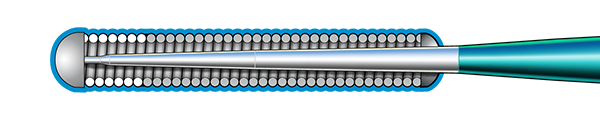

Inner Coil Technology

The advanced design of the stainless steel core and Inner Coil Technology provides a unique combination of exceptional torqueability, rail support, and shape retention.

- Stainless steel inner coil affixed directly to the distal end of the guidewire core

- Improved durability and ease of shaping

- Exceptional torqueability without whipping

Micro EMTTM Technology

MICRO EMT exactly matches the taper of the core and coil, allowing for a lower profile and a more flexible core, leaving almost no room for the core to move within the coil, resulting in 1:1 torque.

- Entry: The smallest tip on the market (0.008”) and the long taper (6 cm) facilitate easy lesion entry in even the most complex lesions.

- Maneuverability: A flexible distal shaft enables excellent intraluminal navigation in complex lesions, with minimal perforation risk.

- Torque: With exactly matched tapers, the core and coil move as one, eliminating whip and empowering precise steerability.